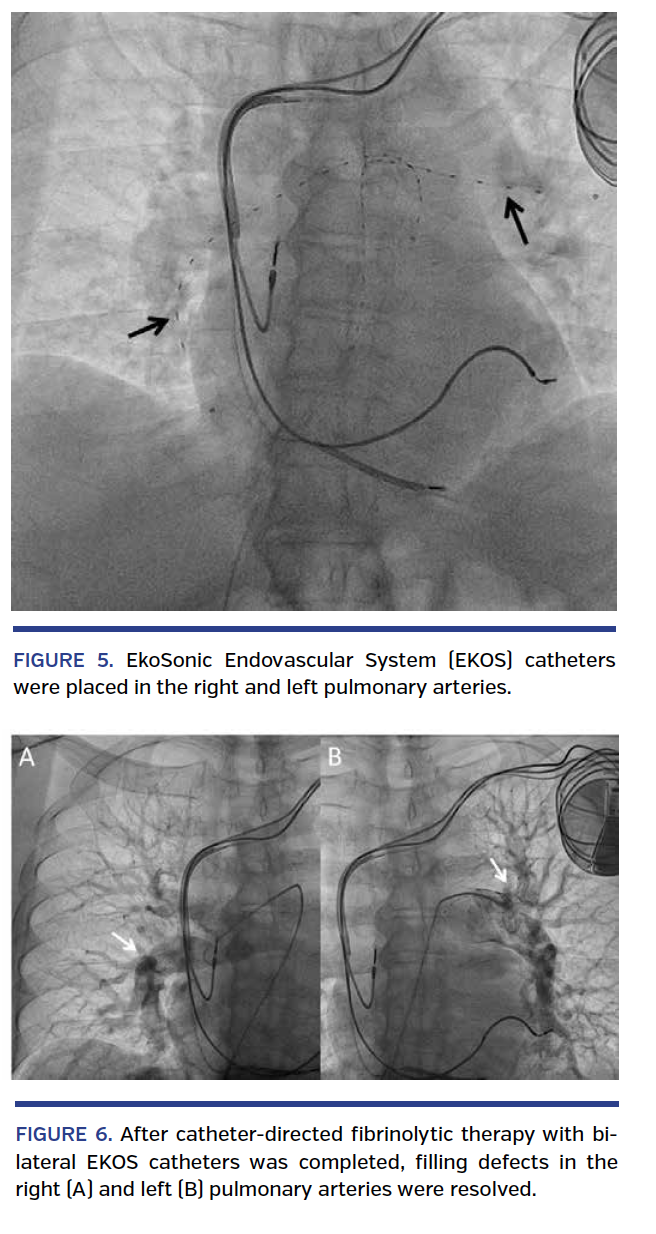

A 76-year-old male presented with a submassive pulmonary embolism (PE) despite having an inferior vena cava (IVC) filter. Contrast-enhanced computed tomographic scan revealed left and right main pulmonary artery emboli (Figure 1). Transthoracic echocardiography revealed moderate right ventricular dysfunction and dilation, and N-terminal proBNP was 3970 pg/mL (reference range, <450 pg/mL). An acute deep vein thrombosis in the left common femoral vein was found by venous duplex ultrasound (Figure 2). Venography showed the IVC filter with struts extending into both the left and right renal veins (Figure 3). Because of the mobile nature of the thrombus and potential for embolization, a new infrarenal IVC filter was deployed below the level of the prior filter. Pulmonary angiography confirmed the finding of bilateral pulmonary emboli (Figure 4). EkoSonic Endovascular System (EKOS Corporation) catheter-directed, low-dose fibrinolysis (total dose, 24 mg) was initiated via bilateral catheters (Figure 5) along with intravenous heparin. Repeat pulmonary angiogram the following day revealed significant improvement of the filling defects bilaterally (Figure 6). The patient was asymptomatic after 12 hours of therapy, and was discharged from the hospital on warfarin.